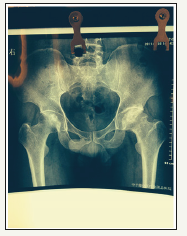

Mr. Lee (fake name) was 39 years old, father of a one-year old baby boy with Torticollis since birth. Baby had Physiotherapy at one of the government hospitals with little progress over the year. So, Lee decided to seek Microcurrent treatment for the baby as recommended by a friend with similar issue. In 10 days, baby was fully recovered [1]. Amazed by the result, Lee asked Milly the therapist if Microcurrent can help regenerate his left Arthritic Hip which affected his daily living- pain even on level ground walking, increase pain with stairs and running, not to mention his favorite ball room dance. Lee has scheduled for a Total Hip Replacement surgery in one week’s time. He was very keen to know if the treatment can help to regenerate the joint to spare him from the surgery, as he was told the artificial joint can only last about 10 years, which means every 10 years he must go under the knife unless there are other new method to combat this condition (Figure 1).

Figure 1:X ray of bilateral hip taken in 2011

Lee returned to China, sent X-ray of the Hip took on July 20, 2014 and forwarded the old X ray taken in 2011 for comparison.

(please refer to inserted X-ray)

One can see significant improvement of the joint line and increased of joint space to normal which means the cartilage has been regenerated to fill up the joint space.